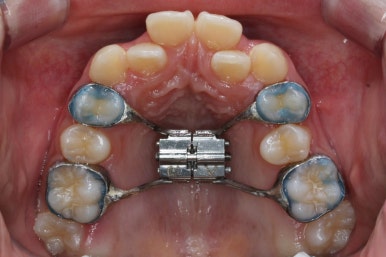

처음 내원 때의 입안 모습입니다.

영구치는 모두 맹출이 되어있었고 아랫니는 윗니에 비해 매우 가지런한 편이였습니다.

윗니 중에서도 앞니가 매우 삐뚤하고 특히 작은 앞니 양쪽 모두가 아래 앞니보다 안쪽에 들어가 있는 모습입니다.

치료 첫 단계는 좁은 취턱뼈를 넓혀주는 악궁확장장치(RPE)를 사용했습니다.

단순히 윗니가 삐뚤하여 자리를 확보하는 목적으로 사용하는 건 안됩니다. 아래에 비해 위쪽 치아들이 좁게 배열이 되어 있다면 시행하게 됩니다.